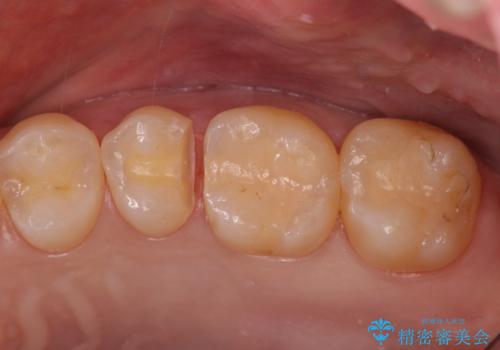

歯と歯の間の虫歯 セラミックインレーでの治療

- 検査の結果、歯と歯の間に虫歯が見つかった患者様です。

白く目立たないものでの治療をご希望されたため、セラミックインレーでの治療となりました。

- 左上5 セラミックインレー 77,000円費用は治療当時の料金となります